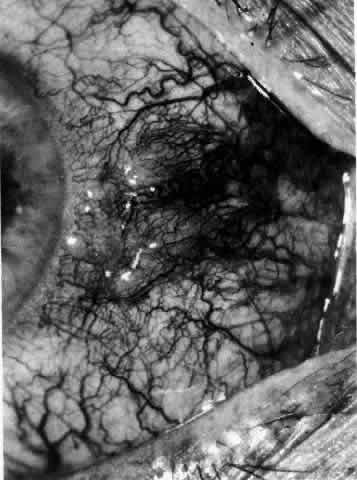

The redness of simple episcleritis may be intense, varying from a fiery-red or a brick-red discoloration to a mild red flush, but it does not have the bluish tinge that is seen in scleritis. The distribution is usually sectorial but can involve the whole anterior segment of the globe. The episcleral vessels are engorged but retain their normal radial position and architecture (Figs. 13 and 14; Color Plate 1A). In simple episcleritis, there is a diffuse edema of the episcleral tissues. These tissues are sometimes infiltrated with gray deposits that appear yellow in red-free light. Surprisingly, the eye is rarely tender to the touch.

Fig. 13. Infiltration of the episclera in which the superficial episcleral vessels show maximal congestion. Conjunctival vessels are slightly congested, as is the deep episcleral plexus, whose irregular criss-cross pattern can be seen deep to the radially arranged superficial episcleral plexus.

Fig. 14. Diffuse inflammation. Superficial vessels are maximally engorged and retain their radial pattern and architecture. (See Figures 27 and 34.) (Watson PG: Connective tissue disorders and the eye. In: Recent Advances in Ophthalmology, Vol 5, pp 214–277. London, Churchill-Livingstone, 1975)